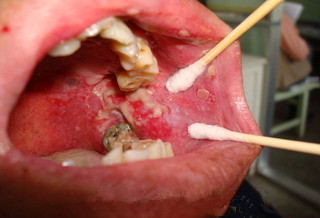

来自南海的区某是一名普通工人,开始出现口溃疡的情况时,他不以为然,认为是上火引起小问题,吃了几天清淡... 【详细】

曹先生,26岁,广州增城人。反复口腔溃疡8年,加重2~3年,患者儿时即溃疡大约如枣,小如绿豆,近年频发,每月... 【详细】